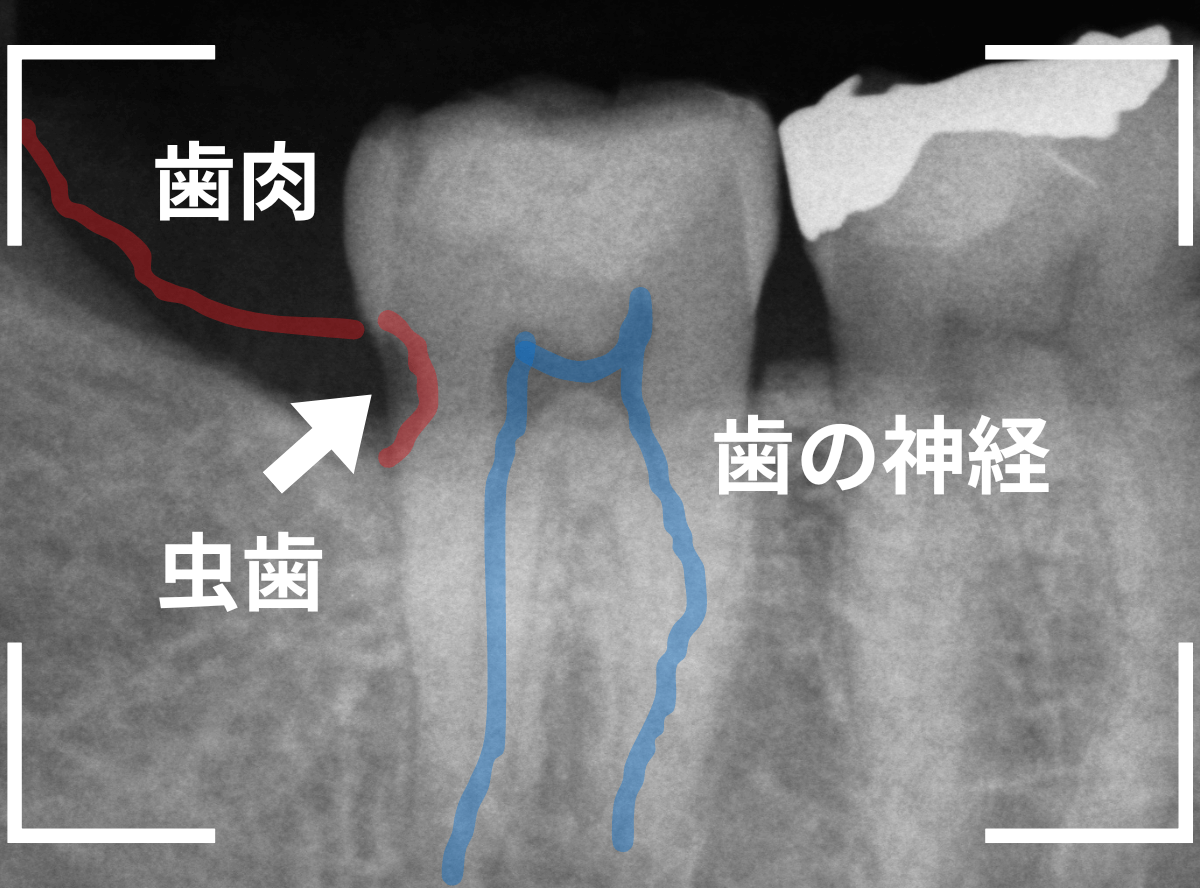

Case.18 おやしらずの抜歯後に歯がしみる

今回は、上のおやしらずが原因で虫歯になってしまった方のケースです。

〇部のおやしらずを虫歯で抜歯しました。

レントゲン写真です。

レジンの下が虫歯になっているのがわかります。

抜歯してしばらく経ったところです。

特に問題なさそうに見えますが、「おやしらずを抜歯してから、歯がしみるようになった」との訴えです。

これは、おやしらずを抜歯した後によくある症状です。

レントゲン写真で確認します。

青い線が歯の神経、赤い線が虫歯です。

おやしらずがあった際にはわかりづらかったですが、歯の後ろ側のおやしらずが重なっていたところが虫歯になっているのがわかります。

おやしらずが原因で、このように手前の歯が虫歯になってしまう事が多いために、抜歯を勧められる事が多いのです。

そして、虫歯の部分におやしらずが被さっていたために、しみる症状などを感じなかったのです。